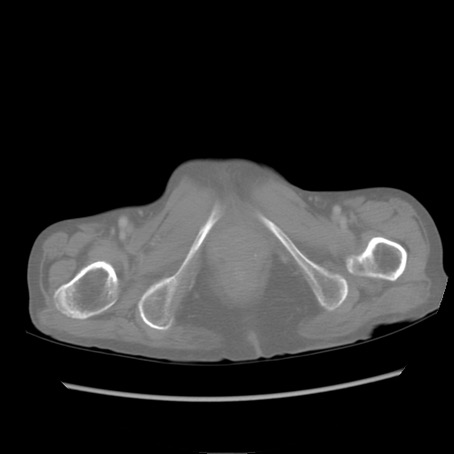

冠状断像